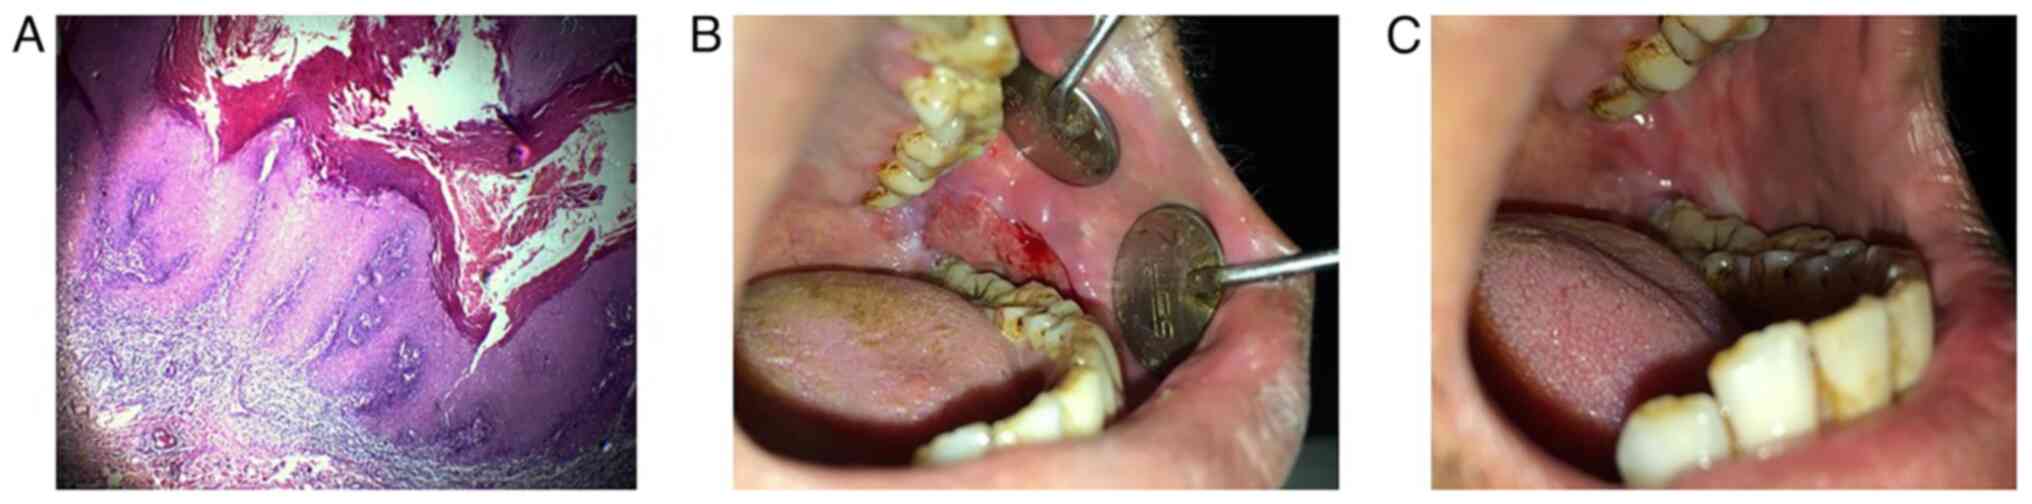

Figure 1

(A) Proliferative lesion over the left buccal mucosa. (B) Image of the excised lesion. (C) Reconstruction of the defect using the buccal fat pad (the yellow arrow depicts the source of the buccal fat pad).

The lesion was managed by a wide local excision under local anaesthesia and the sample was sent for histopathological analysis to the Oral Pathology Department of Sharad Pawar Dental College, Wardha (Fig. 1B). Tissues were stained using Harris' haematoxylin solution at a temperature of 60-70˚C for 6 h and then rinsed under tap water. Subsequently, 10% acetic acid and 85% ethanol were used to differentiate the tissue twice for 2 and 10 h followed by rinsing with tap water again. The tissues were saturated in lithium carbonate solution for 12 h and then rinsed. Final staining was carried out with eosin Y ethanol solution for 48 h. Tissues were dehydrated using 95% ethanol twice for 0.5 h followed by soaking in xylene for 1 h at 60-70˚C and then paraffin for 12 h. Slices (12-µm-thick) were sectioned from the stained samples, dewaxed, mounted and imaged using a Nikon NIS-Elements microscope at x4 magnification. A histological examination depicted a parakeratinized epithelium with long, broad pushing rete pegs and a parakeratin layer exhibiting a typical chevron pattern with scanty connective tissue. The epithelium exhibited basal cell hyperplasia, a loss of stratification, acanthosis, individual cell keratinization, cellular and nuclear pleomorphism at places and minimal abnormal mitotic figures (Fig. 2A). Depending on the histopathological features, the final diagnosis of oral VH was made. Reconstruction of the defect was performed using the BFP (Fig. 1C). The BFP was used due to its higher vascularity, its proximity to the donor site and to provide less scar contracture.

Figure 2

(A) Histopathological image demonstrating a parakeratinized epithelium with long, broad and pushing rete pegs and a parakeratin layer, exhibiting a typical chevron pattern (original magnification, x4; haematoxylin and eosin staining). (B) Post-operative image at 14 days exhibiting satisfactory healing. (C) Post-operative image at 3 months, exhibiting mucolisation of the buccal fat pad.

The patient was recalled for regular follow-up. After 2 weeks, the surgical site was in a healthy condition with uneventful healing (Fig. 2B). At the end of 3 months, the BFP exhibited complete mucolisation (Fig. 2C). The patient remains on follow-up and there are currently no signs of recurrence even after 2.5 years.